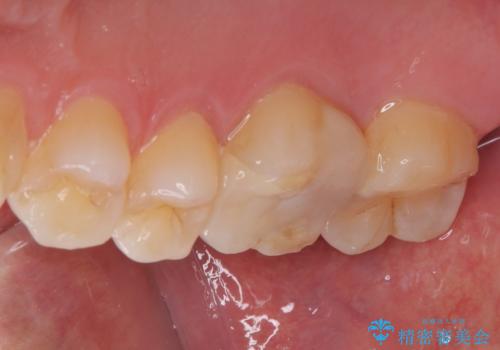

拡大鏡視野下で虫歯、古いプラスチック(コンポジットレジン)を除去し、ハイブリッドアンレーに適した形に整えました。

歯と歯茎の間に圧排糸と言われる糸を入れてシリコーン印象材にて型どりをしました。